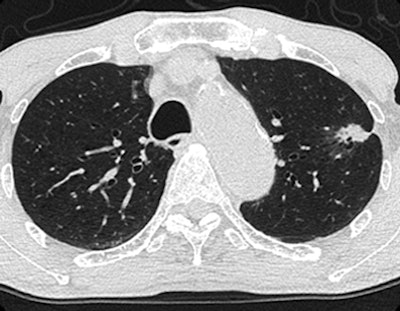

| Axial images of primary lung cancer (adenocarcinoma) in left upper lung lobe in 76-year-old man. Above, thin-section CT image shows nodule 18 mm in diameter in left upper lobe. Below, perfusion map shows nodule has high perfusion, with PFMS (scale at left) determined to be 89.9 mL/100 mL/min; this is a true-positive case according to maximal slope method results. Bottom, integrated PET/CT image shows high uptake of FDG, with SUVmax of lesion determined to be 3.8, indicating a true-positive case. Images republished with permission of the Radiological Society of North America from Radiology, February 2011, Vol. 258:2, pp. 599-609. |